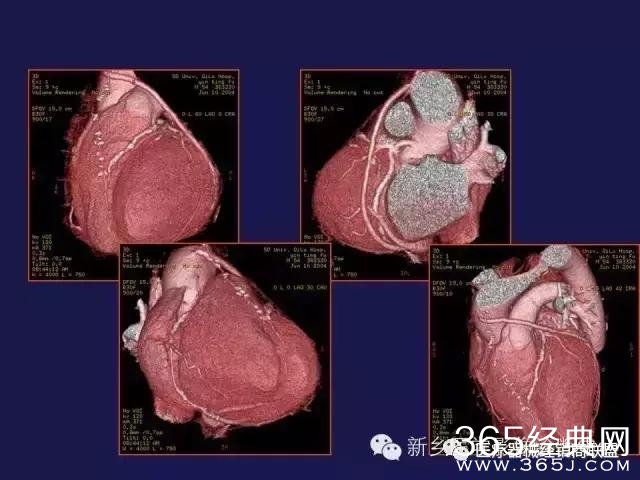

CT、MRI很难?NO,今日我们一起来学习一下如何读CT、MRI!

内行看门道:

整整90张图

强烈建议大家收藏后再观看